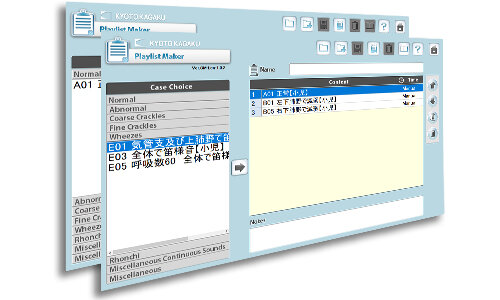

プレイリスト作成機能

実習内容に合わせて再生リストが作成ができます。